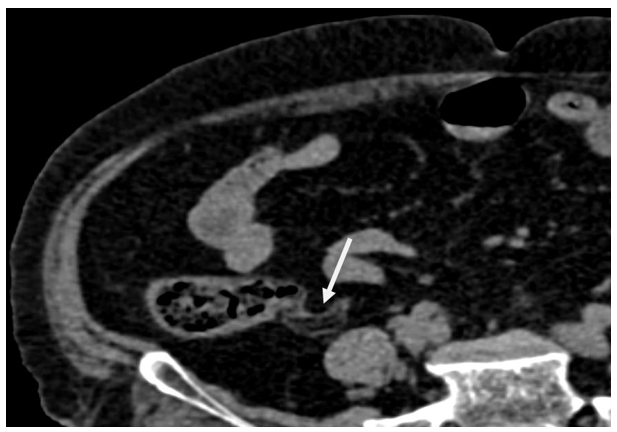

Do ponto de vista diagnóstico, métodos de imagem exercem papel central na identificação dessas lesões. A tomografia computadorizada (TC) costuma revelar massas extramucosas bem delimitadas com atenuação de gordura (entre -80 a -120 unidades Hounsfield), geralmente sem sinais inflamatórios periapendiculares (Figura 1). Da mesma forma, em ressonância magnética observa-se sinal elevado nas sequências ponderadas em T1 e T2, com supressão de sinal nas sequências com saturação de gordura, características indicativas de infiltrado adiposo difuso (Biswas; Supryia, 2024). Na colonoscopia, lipomas submucosos podem ser reconhecidos pelos sinais clássicos de “tenting” (tracionamento da lesão pela pinça formando um chapéu de bispo), “cushion” (consistência macia e deformável à pressão) e “naked fat” (extrusão de tecido gorduroso amarelo após biópsia superficial) (Taylor; Stewart; Dodds, 1990). Apesar desses avanços, o diagnóstico de lipomatose intestinal ainda é frequentemente incidental. Devido à raridade de sua apresentação e ao pequeno número de casos descritos na literatura até o momento, apresentamos o relato de um caso de lipomatose do apêndice cecal diagnosticado por exame anatomopatológico, com o objetivo de caracterizar esse evento incomum e auxiliar na identificação de suas alterações microscópicas.

Achados Macroscópicos: o espécime consistia em apêndice cecal íntegro medindo 3,5 × 1,2 × 0,6 cm, revestido por serosa de aspecto congesto e com acúmulo evidente de tecido adiposo em sua parede (Figura 2). À secção, a parede mostrava espessura aumentada (cerca de 0,5 cm) e a luz apendicular encontrava-se dilatada e preenchida por material macio de coloração amarelada, sugestivo de conteúdo gorduroso.